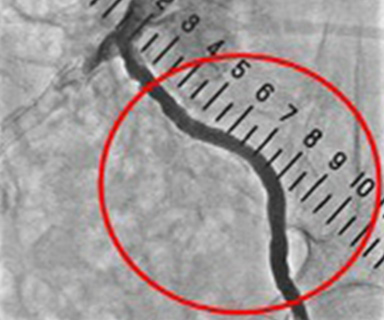

この検査では閉塞性動脈硬化症の原因となる足へ流入する動脈が狭くなっているか、閉塞しているかを調べます。

閉塞性動脈硬化症になると足のへの血流量が減り、足の冷感・しびれ・痛みなどがあらわれ、ひどくなると潰瘍や壊死を起こすこともあります。また検査だけではなく狭くなった動脈を拡げる治療も行うことができます。

カテーテル操作をしやすい太い動脈(主に足の付け根)へ麻酔をし、そこからカテーテルを入れます。

狭くなった血管へカテーテルを進め、風船のついたカテーテルを膨らませ血管を拡げます。膨らませるだけでなくステントと呼ばれる金属のバネで固定し血管を拡げることもできます。

これを経皮的経管的血管形成術(PTA:percutaneous transluminal angioplasty)と呼びます。

治療前

(左内腸骨動脈造影)

風船治療・ステント挿入

治療後

(左内腸骨動脈造影)

膝付近の狭くなった動脈

(下肢動脈造影)